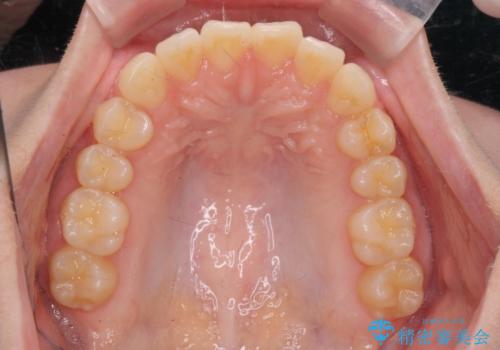

前歯のねじれをマウスピース矯正で治したい

- 前歯のねじれや がたつきを治したい、マウスピース矯正治療を希望され来院されました。

初診時程度のがたつきやねじれであれば、26枚以下のマウスピース矯正 モデレートプランで、比較的リーズナブルに矯正治療を受けていただくことができます。

実際の治療期間は約半年で仕上がりのような綺麗な歯並びを手に入れることができました。